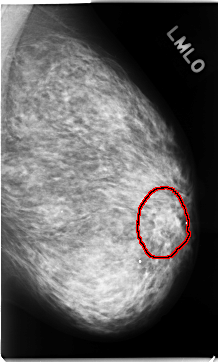

C_0130_1.LEFT_MLO

LEFT_MLO LINES 4704 PIXELS_PER_LINE 2824 BITS_PER_PIXEL 12 RESOLUTION 50 OVERLAY

FILE: C_0130_1.LEFT_MLO.OVERLAY

TOTAL_ABNORMALITIES 1

ABNORMALITY 1

LESION_TYPE MASS SHAPE IRREGULAR MARGINS ILL_DEFINED

ASSESSMENT 4

SUBTLETY 1

PATHOLOGY MALIGNANT

TOTAL_OUTLINES 1

BOUNDARY